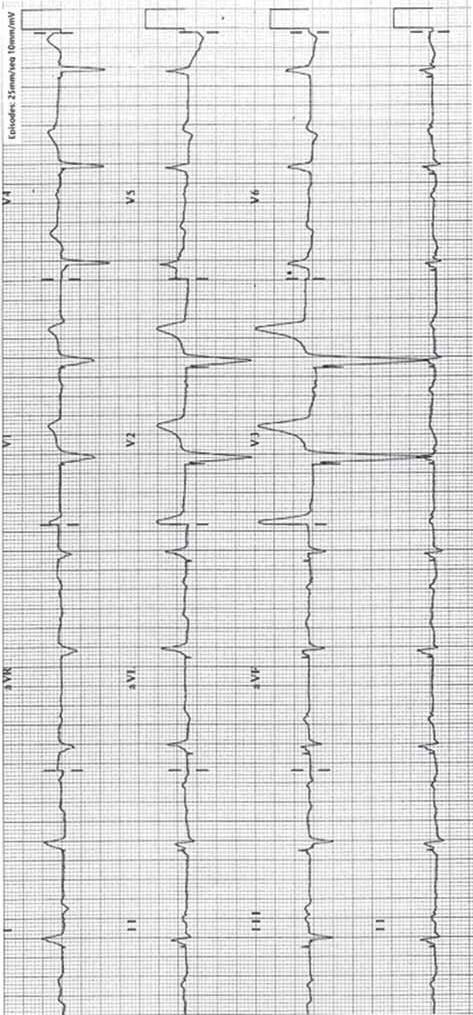

Rycina 13.4 Rycina 13.5

Rycina 13.7

Rycina 13.11

Rycina 13.12

Rycina 13.13